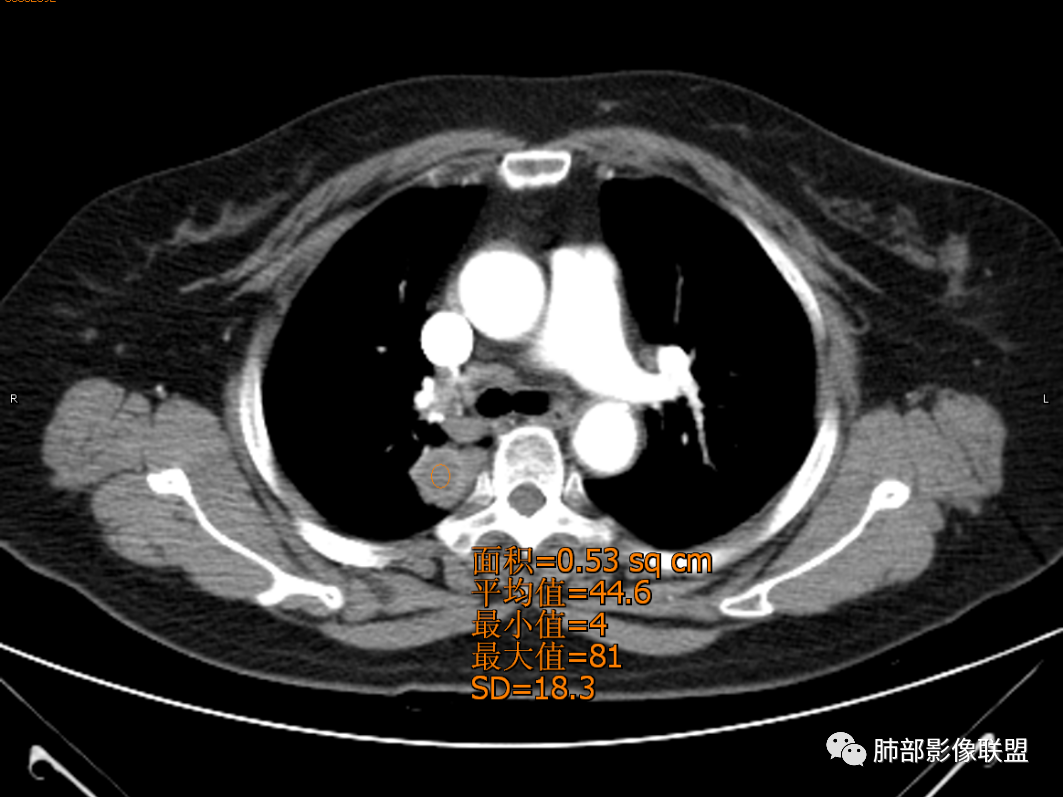

张小兵:坏死为软组织密度44.5Hu,边界清楚,厚薄均匀,符合结核的干酪性坏死。

大雄:平扫 40多 ,是凝固性坏死,所以不支持肺脓肿

岁月:病史:咳痰血1月,右上叶占位,无发热盗汗;女,cea,角蛋白,nse正常影像:右上叶后段,后段支气管略窄,右肺门钙化,该处淋巴结成团,形态可辨认病灶边缘有钙化,周边高密度中间低,密度不均,芋艿子,中心44.6hu,边缘有强化,环状,应该较高。周边有点,平直,无毛刺,像棘角,有轻度牵拉毛刺软,血管推移。诊断:良性结节,结核。

1.女性,咳嗽咳痰痰中带血1月。血常规、肿瘤标记物正常。             2.CT示右肺上叶不规则肿块,边缘以平直收缩为主,可见U型凹陷及桃尖征,周围见边缘模糊的GGO,软毛刺,从形态学的角度病灶更支持炎性改变; 3.增强呈薄壁环形强化,壁光整、清楚,也支持炎性改变;病灶内部平扫CT值密度比较高,约40HU,明显高于水的密度,而且未见强化,提示病灶的坏死可能为凝固性坏死;    4.从上面的分析,病变更符合炎性,患者白细胞不高,治疗后没有好转,不支持普通细菌的感染;影像病灶较局限,边界较清楚,病灶慢性炎症或肉芽肿,形态机发病部位更符合继发性肺结核。患者非易感人群,病灶孤立,尽管有液化,也很难第一时间考虑真菌,尤其是曲霉菌感染。什么是炎性肉芽肿?炎性肉芽肿的常见疾病谱系有哪些?那什么是凝固性坏死和干酪样坏死?跟一般的液化性坏死有什么区别?接下来我们逐一学习一下。

凝固性坏死是由于蛋白质变性凝固且溶酶体酶水解作用较弱,坏死组织水份少,坏死区表现出灰黄、干燥、实质的状态,常出现在心、肝、肾、脾等实质性器官因缺血缺氧、细菌真菌毒素、化学腐蚀作用引起,坏死灶与正常组织之间分界很清楚。干酪样坏死是凝固性坏死中坏死更为彻底的特殊类型凝固性坏死,主要见于结核杆菌感染,坏死组织因含较多脂质,色微黄,外观似干酪状。液化性坏死是由于坏死组织中可凝固的蛋白质少,自身释放了大量的水解酶,组织发生液化溶解,坏死组织水份多,常见于细菌感染引起的脓肿、脑软化等。  所以凝固性坏死CT值往往比水的CT值高,部分干酪样坏死因为含有大量脂质,可以CT值比较低,甚至现负值。部分液化坏死CT值接近水。注意坏死区域CT值还受时段及成分影响。  由于凝固性坏死含水少,蛋白含量多,所以在MR的T2W图像上表现为等或稍低信号,而液化坏死含水量多,MR信号类似水信号,T2W图像上表现高信号。